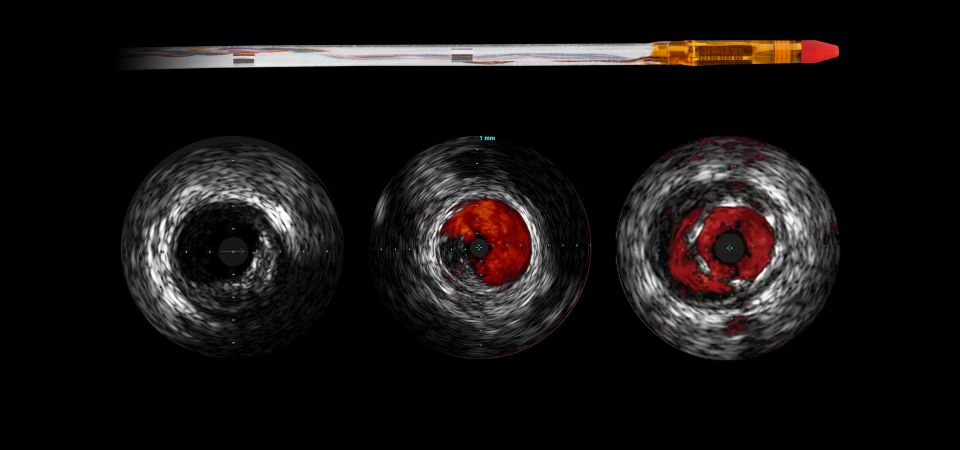

Eagle Eye Platinum St Digital Ivus Short Tip Catheter Philips